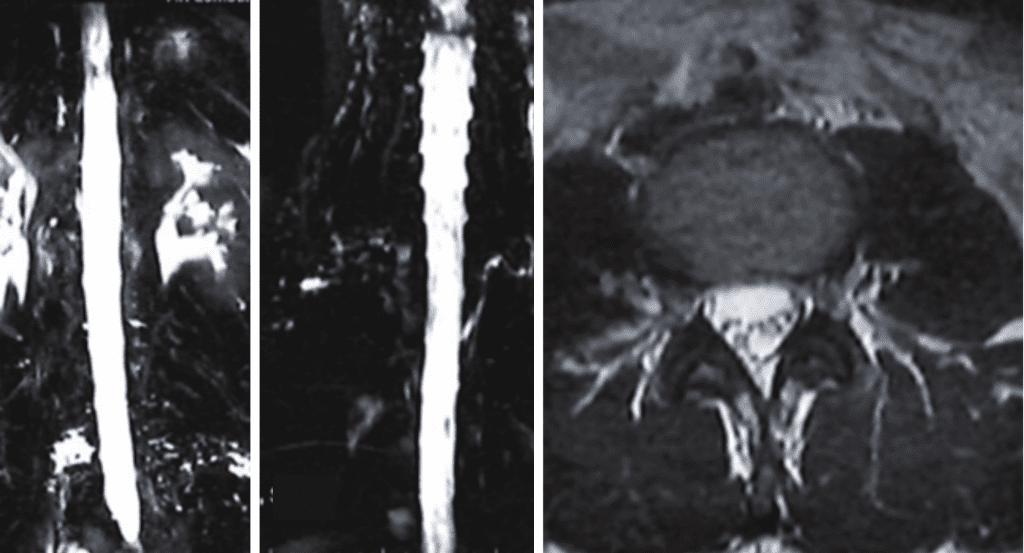

As in her case, MRI imaging, with heavily weighted T2 Fat-Saturated Sequences (3D-T2WI-FS) provide a very high accuracy for the CSF leak presence into the epidural space. Multiple imaging sites are usually identified, although at surgery or with dynamic CT myelography, only one site is found.

Fig 1. MRI myelogram with fat saturation showing multiple fluid areas along nerve root areas in the high and low lumbar region, consistent with CSF leaks.